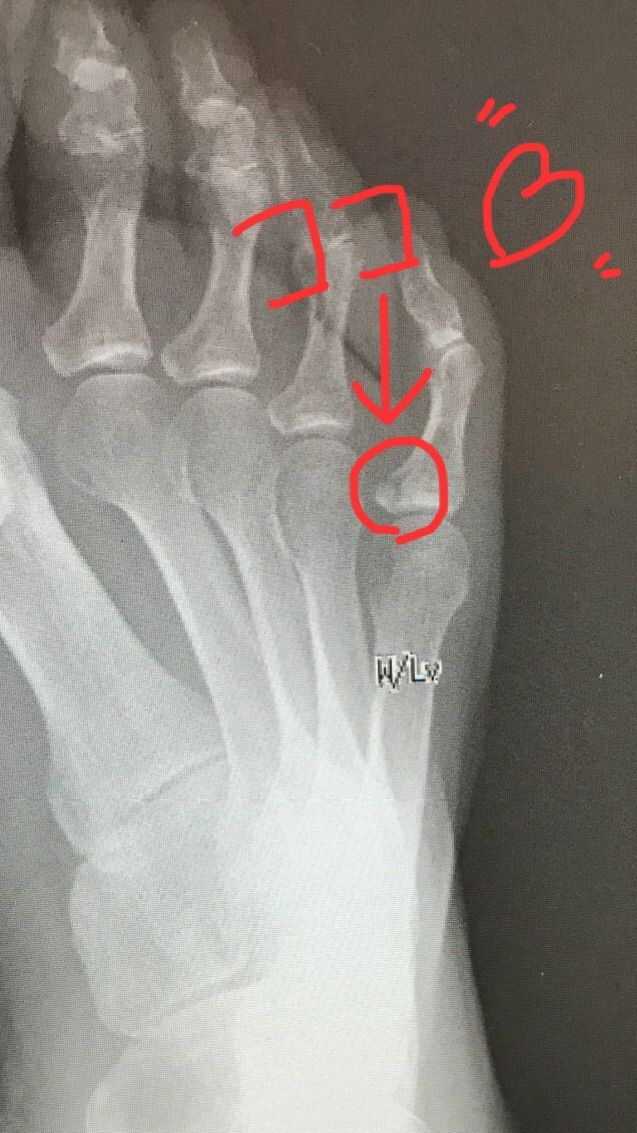

小指の関節部分が骨折していました(TT)

基節骨骨折…と言う診断結果でした。